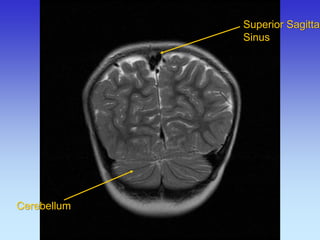

Superior Sagittal Sinus

Cerebellum